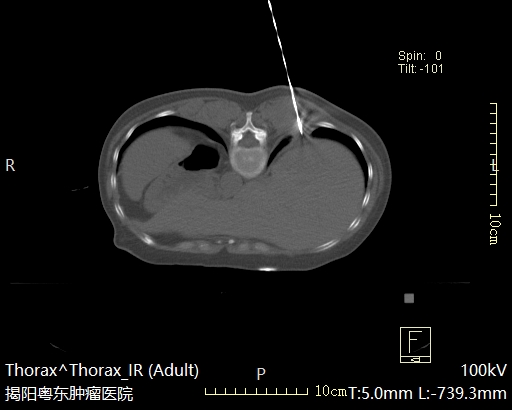

肺结节消融治疗

放射性粒子植入治疗